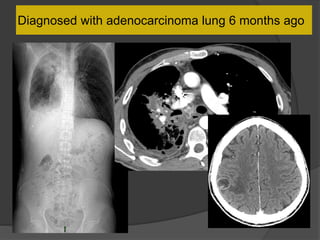

Diagnosed with adenocarcinoma lung 6 months ago

Case 2 Diagnosis: “Cocoon

peritonitis”

•AKA sclerosing

encapsulating peritonitis

•Rare cause of bowel

obstruction due to fibrotic

encapsulation of the bowel

forming a sac or cocoon

•May be idiopathic or

secondary to chronic

peritoneal dialysis, TB,

sarcoidosis, GI malignancy,

fibrogenic foreign material

•Treatment –Surgical

removal of the covering

membrane

Hong Kong Med J 2012